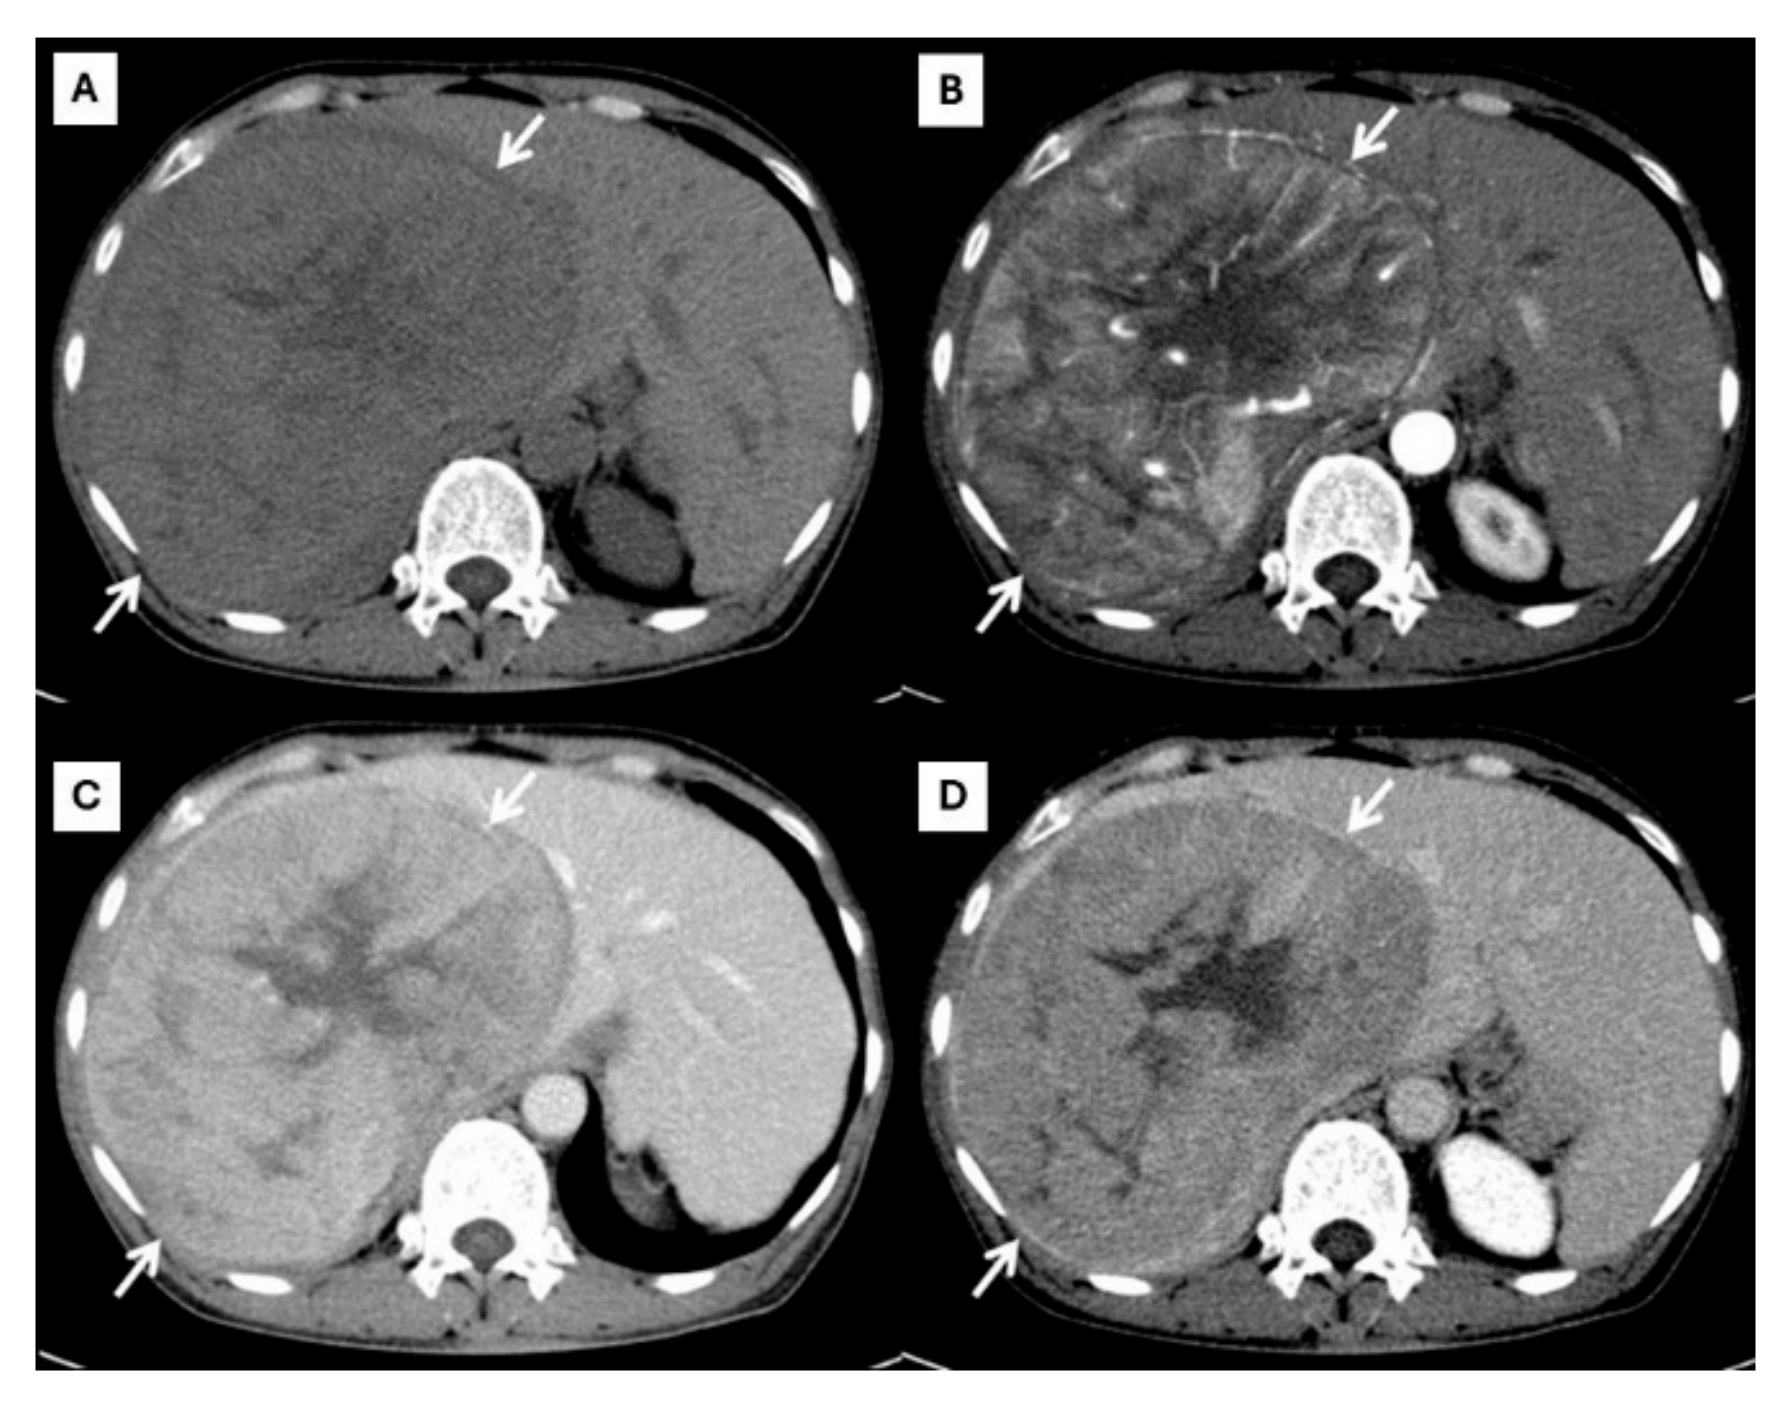

Figure 3.

CT findings of atypical HCC. Pre-contrast (A), arterial (B), portal venous (C), and delayed (D) post-contrast sequences demonstrate a mass with rim-like enhancement at the tumor periphery during the arterial phase ((B), arrow) and progressive centripetal enhancement in the later phase ((C,D), arrow).